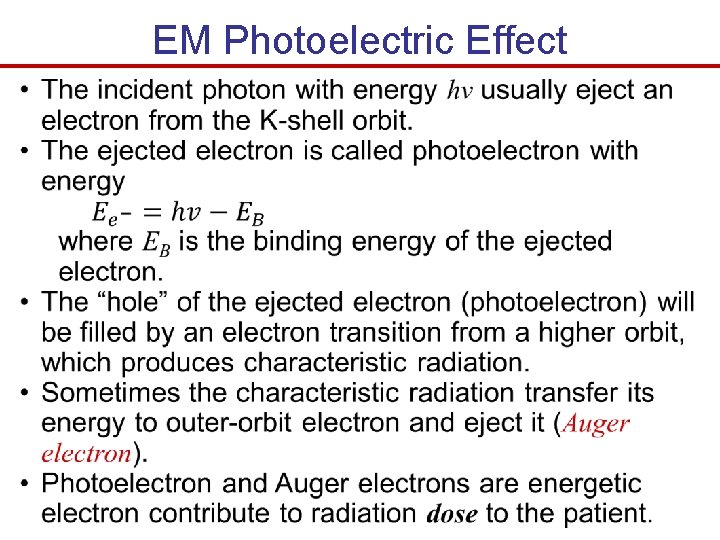

Primary Electromagnetic Radiation Interactions The three main mechanisms by which EM ionizing radiation interacts with materials to from images are: 1. The photoelectric effect - Incident x-ray photon totally loss energy to the atom’s electron cloud. - Provide contrast between different types of tissues in the medical image. 2. Compton scatter - Incident x-ray photon partially loss energy to the atom’s electron cloud and change direction. - Limit the resolution of x-ray images. 3. Pair production (need high energy 1. 02 Me. V so it isn’t applicable in medical imaging 25 - 500 ke. V).

Primary Electromagnetic Radiation Interactions photoelectric effect Compton scattering Figure 4. 6 The photoelectric effect, shown in (a) and (b), and Compton scattering, shown in (c).

EM Photoelectric Effect